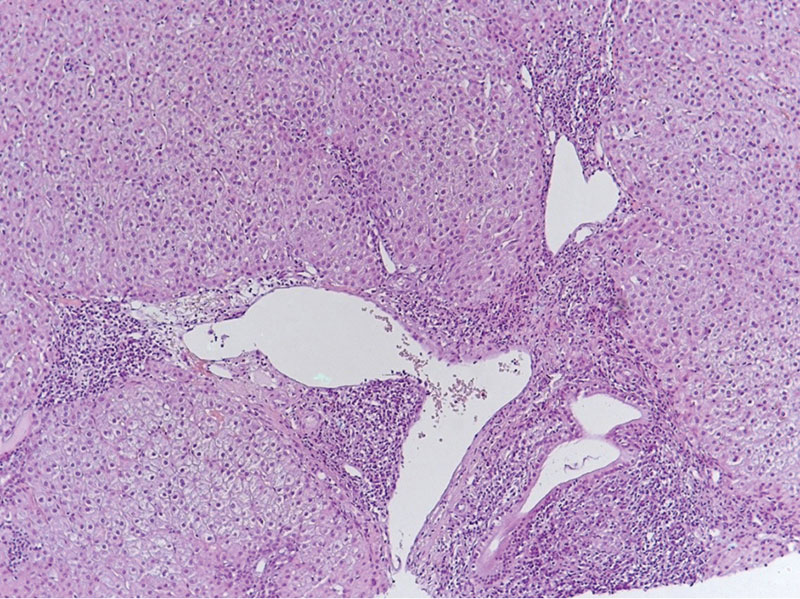

Рис. 2. Деструкция желчных протоков и формирование эпителиоидноклеточных гранулем. Увеличение × 300

По результатам гистологического исследования биоптата печени были выявлены как характерные черты ПБХ (деструкция мелких желчных протоков), так и признаки АИГ (ступенчатые некрозы, эмпериополез и лимфоцитарные розетки); заключение морфолога: «Аутоиммунный гепатит умеренной степени активности. Первичный билиарный холангит». Стадия фиброза соответствовала F2 по шкале METAVIR. Индекс гистологической активности (ИГА) по Knodell – 9. Морфологическая картина ткани печени представлена на рис. 1 и 2.